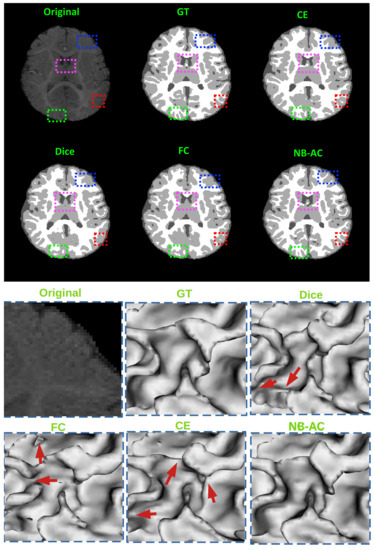

Figure 8, Figure 9, Figure 10 and Figure 11 visualize the comparison between our proposed NB-AC loss against other loss functions including Dice, Focal (FC) and Cross Entropy (CE) on the Unet framework. These images are randomly selected from the testing set of various datasets, namely DRIVE, MRBrainS 2018, BRATS 2018, iSeg 2017. As shown in Figure 1, medical images contain poor contrast images where the boundary between objects is very unclear and weak. Take the iSeg dataset as an example, due to the myelination and maturation process of the infant brain, the boundary between classes in the infant brain in iSeg is very weak, leading to difficulties for segmentation. The segmentation results from different loss functions are visualized in Figure 11(top) with specific differences highlighted in colored boxes. The infant brain MR images (iseg-2017 dataset) have extremely low tissue contrast between tissues; thus, the segmentation results using traditional loss functions (such as CE, Dice, and Focal loss) have large amounts of topological errors (contain large and complex handles or holes) in the segmentation results, such as the WM surface in the Figure 11(bottom) which illustrates an enlarged view of the white matter surface of an infant brain. Figure 11 (bottom) demonstrates that the proposed NB-AC loss function produces less topological errors (i.e., holes and handles), indicated by the red arrows, compared against the existing loss functions. In addition to the 2D view of the brain as in Figure 11, the 3D view of the entire white matter surface, as in Figure 12, demonstrates that the proposed NB-AC loss function produces less topological errors (i.e., holes and handles), indicated by the red arrows, compared against the existing loss functions.

The segmentation results from different loss functions are visualized in Figure 11(top) with specific differences highlighted in colored boxes. Figure 11(down) illustrates an enlarged view of the white matter surface of an infant brain from the regions highlighted in blue boxes of Figure 11(top). Figure 11(down) demonstrates that the proposed NB-AC loss function produces less topological errors (i.e., holes and handles), indicated by the red arrows, compared against the existing loss functions. For a more detailed visualization, we provide the entire view of the white matter surface obtained from different loss functions in Figure 12.

Figure 11. top: Comparison of our proposed NB-AC loss against other loss functions on the iSeg17 dataset with colored boxes highlighting specific differences. bottom: A closer look is also given with the topological errors indicated by red arrows.